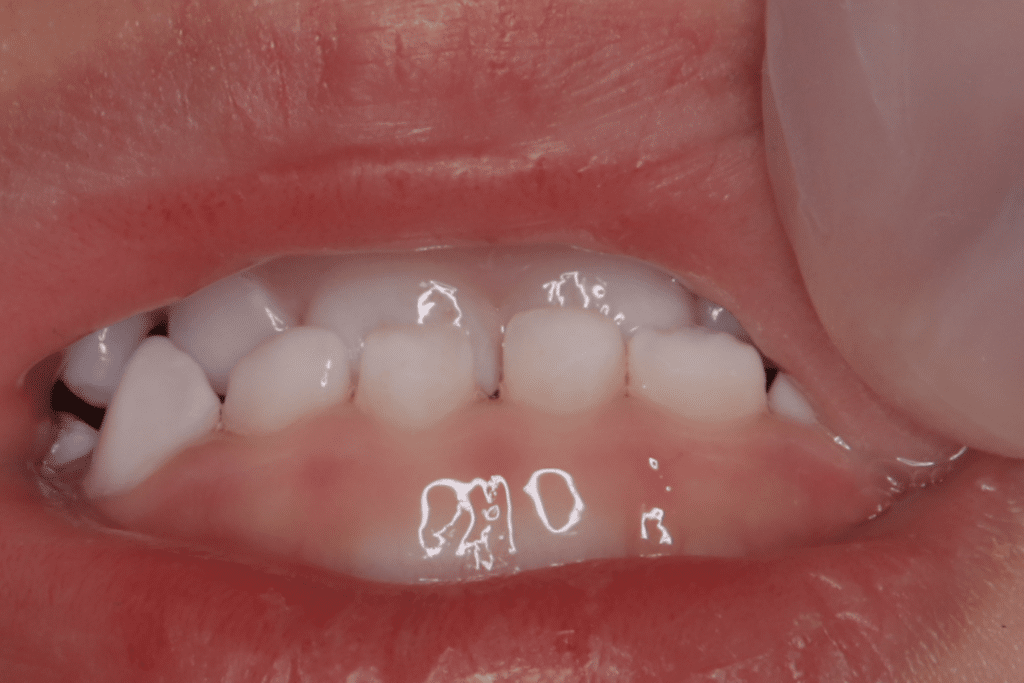

反対咬合(受け口)についての症例1

反対咬合 症例 Case 1

2歳6ヶ月から開始

主訴:反対に噛んでいる噛み合わせを治したい

診断名:反対咬合(骨格性)

治療装置:マウスピースを使用し筋機能療法も併用

反対咬合の改善

【まとめ】

症状:反対咬合

期間:1年4か月

開始年齢:(2歳6ヶ月)~

終了年齢:(3歳10ヶ月)

費用の概算:50〜70万